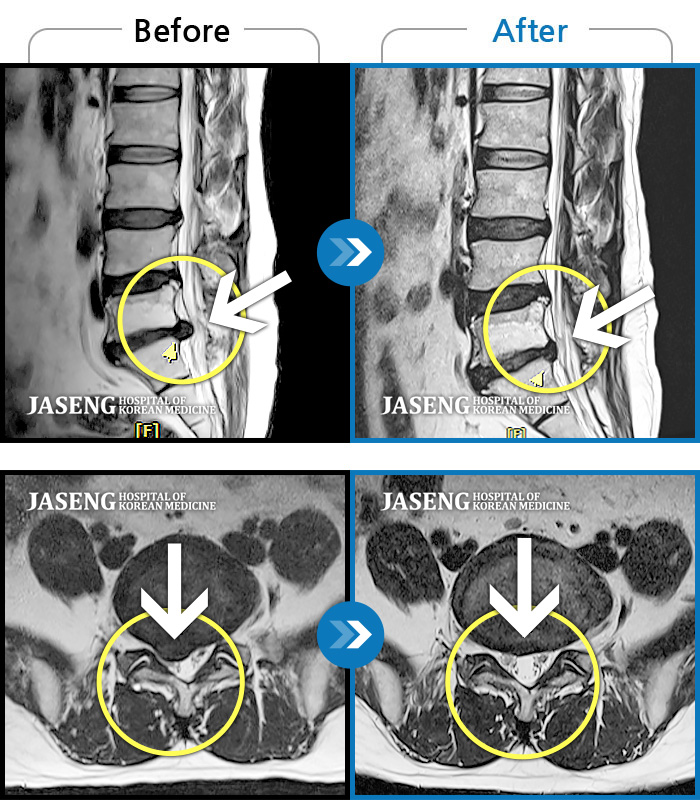

허리디스크

도움받은 사례

광주 · 장영우 원장

양측 허리 통증과 좌측 허벅지부터 발바닥까지 송곳으로 찌르는 듯한 통증 지속되어 내원하셨습니다.

촬영시기

2023.12.26 ~ 2024.12.05